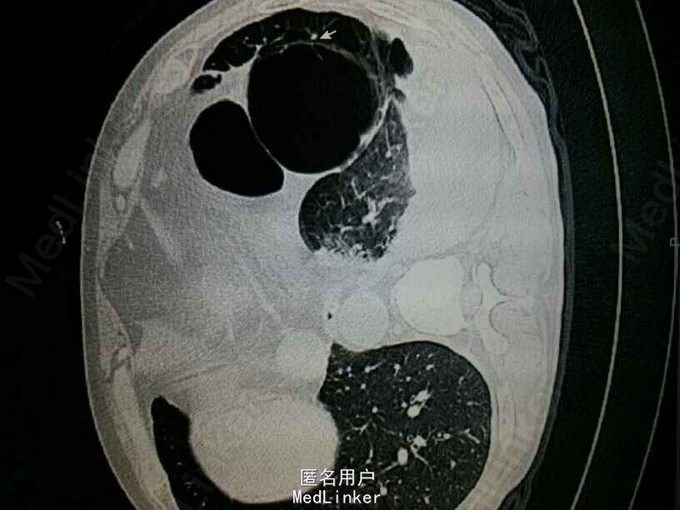

查体:左肺叩诊鼓音,左肺呼吸音低,左下肺可问及少量湿啰音。 辅助检查: CT提示:左肺多发大小不等的囊状气腔,部分病灶壁较厚,可见液平。左肺可见斑片状渗出。左侧胸腔积液。考虑左肺多发肺大泡伴感染,左侧胸腔积液。双肺气肿。

诊断: 肺大泡 肺部感染 胸腔积液 入院以后一直体温高,最高可达39.9度,予头孢呋辛及泰能抗感染治疗,体温无法好转,考虑肺大泡内部并发感染及脓液,予胸腔闭式引流,见较多积脓引出,十余天抗感染后体温白细胞逐渐改善,并行左侧剖胸粘连松解肺大泡切除